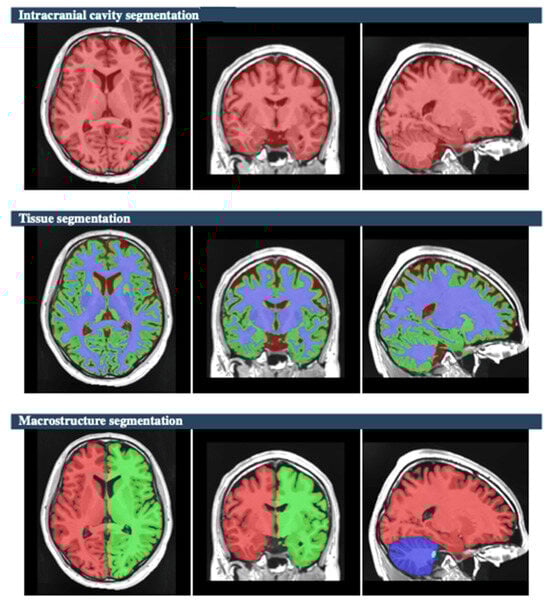

The raw data of MR brain images were analyzed using volBrain Online software that is an automated and online MRI brain volumetry system (https://volbrain.net/, accessed on 1 December 2024). AssemblyNet, VolBrain and HIPS-monospectral pipelines were used to assess brain tissue, subcortical structures and hippocampal subfields, respectively. The high resolution T1-weighted imaging volumes underwent standard pre-processing steps: denoising, coarse inhomogenity correction, MNI space registration, fine inhomogenity correction and intensity normalization. Then, the segmentation process was applied, which consists of the following steps: spatially adaptive non-local means denoising, rough inhomogeneity correction, affining registration to MNI space, fine SPM-based inhomogeneity correction, intensity normalization, non-local Intracranial Cavity Extraction (NICE), tissue classification, non-local hemisphere segmentation (NABS) and non-local subcortical structure segmentation, as depicted in Figure 1.

Figure 1. The process of non-local Intracranial Cavity Extraction (NICE), tissue classification, non-local hemisphere segmentation (NABS), and non-local subcortical structure segmentation [subject 10]. In the segmentation of the intracranial cavity, cerebral tissue is represented in red. For tissue segmentation, grey matter, white matter, and cerebrospinal fluid are indicated by light green, purple, and brown, respectively. In macrostructural segmentation, the right and left hemispheres are colored red and green, respectively, while the cerebellum is shown in blue.